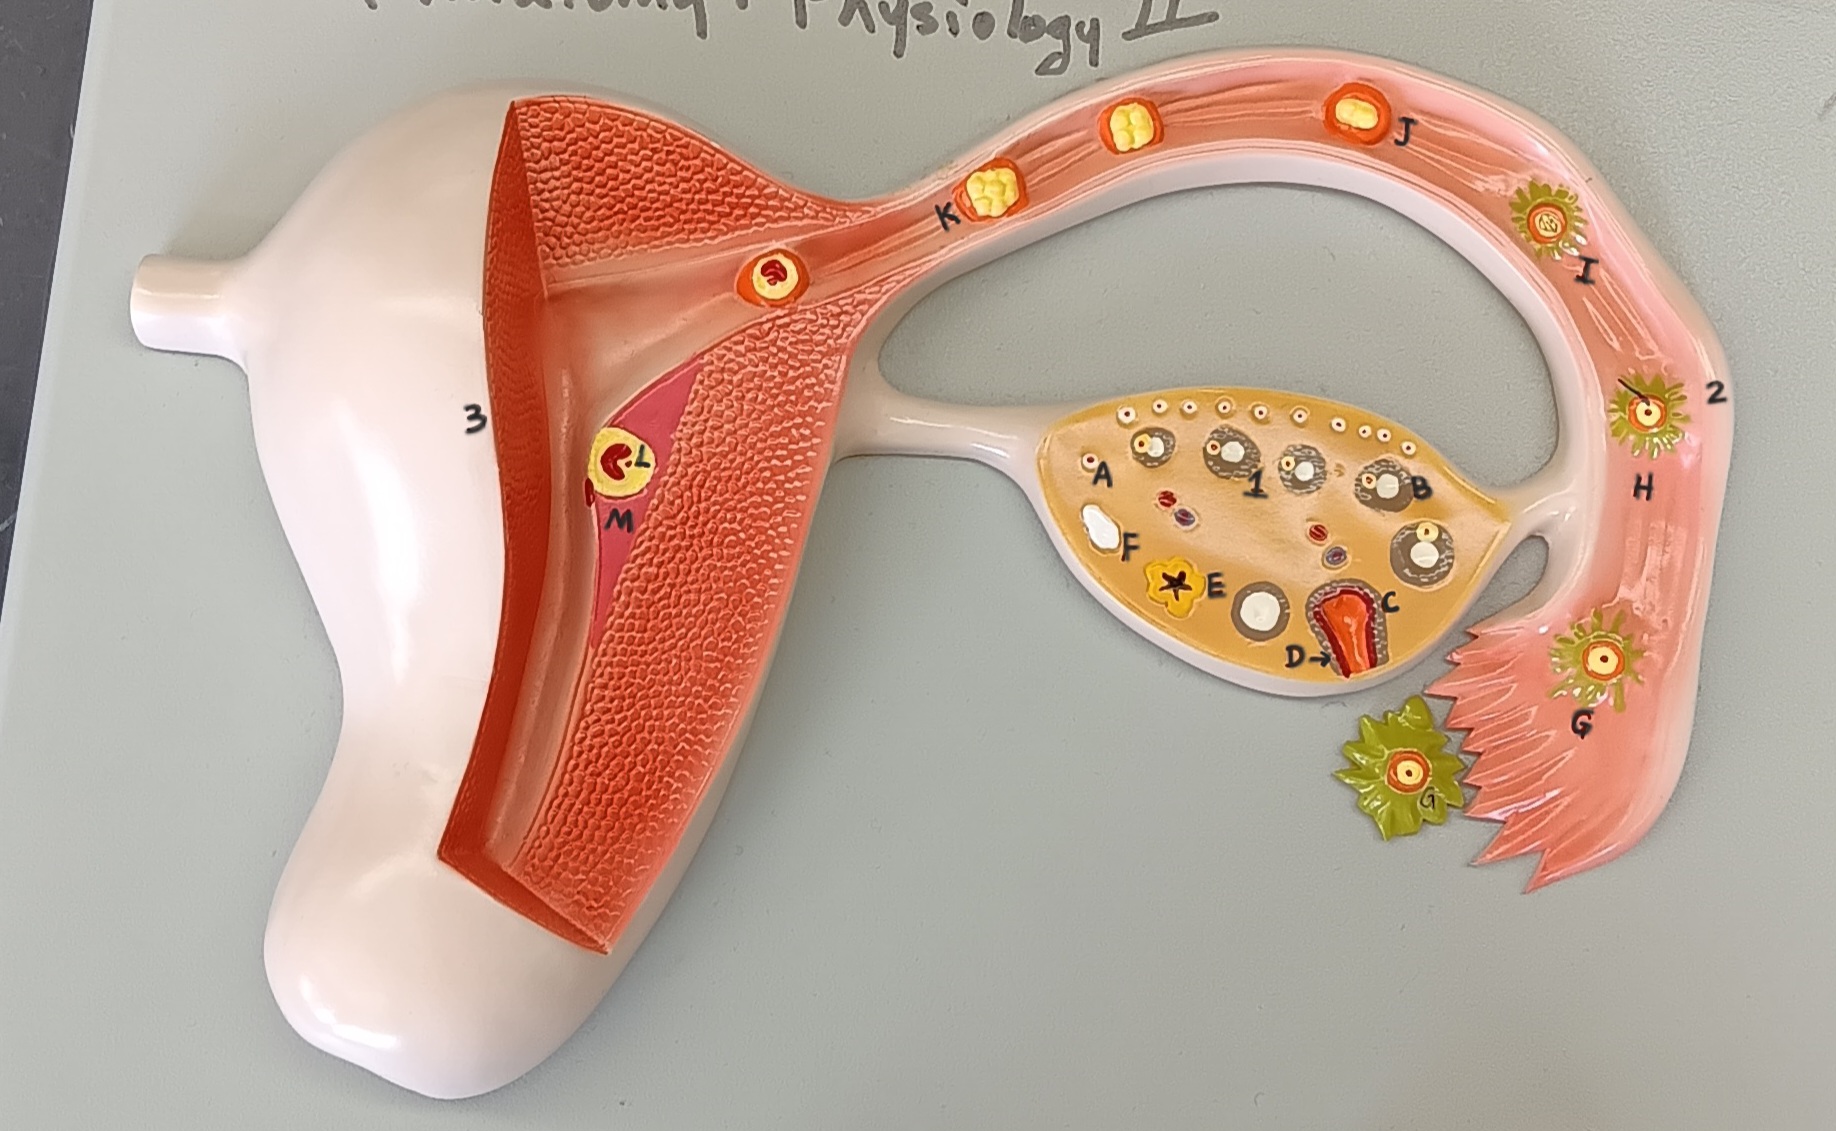

ovary

1

primordial follicle

a

secondary follicle

b

ruptured follicle

c

granulosa cells

d

corpus luteum

e

secondary oocyte

g

ovum

h

zygote

i

blastocyst

l

endometrium

m

corpus albicans

f

uterus

3

fallopian tube

2